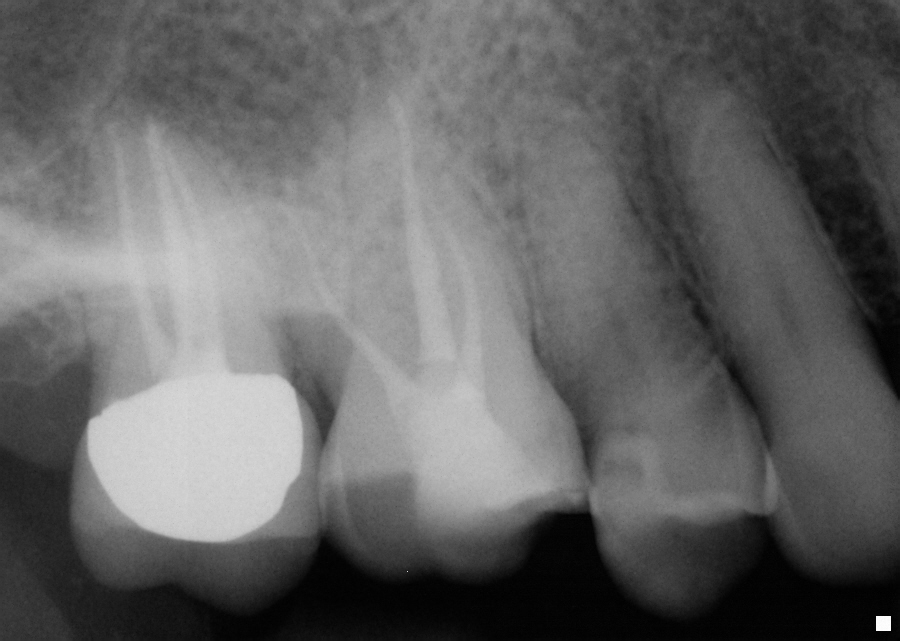

Tooth very calcified and could not get even a 06 in after unroofing. Looked more fin like then separate canal. Interesting that when I seated cone with sealer in MB1 some sealer squirted out MB2 orifice. Obviously they joined somewhere.